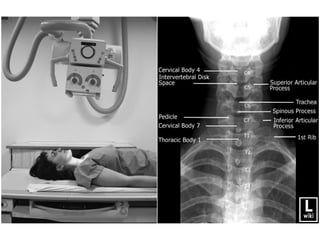

Cervical Spine-Trans-Lateral

Position

• Make the patient to lie on the x-ray table in supine position.

• Hands are kept at side of the body.

• Ensure there is no rotation of the head & neck without much

pressure to the injury neck & foam pads are kept for immobilization.

• Radiation Production given to the patient.

Tube Centering

• Center to the horizontal beam to the cassette at level of C4.

Cassette centering

• Cassette is kept at side of the shoulder of one inch above

the pinna.

Exposure Settings

Distance Focal Spot Grid kV mAs

Tube

Angulation

Cassette

Size

5 Feet Large No 55 24-32 No 8"X10"

Swimmers View